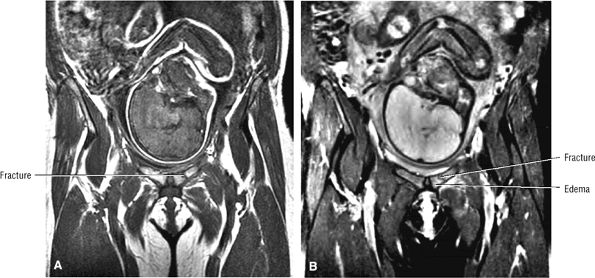

FIGURE 3.28 ● Normal coronal anatomy of the hip. (A, B) In the setting of pubic rami fractures, the sacrum and sacroiliac joints should be examined for the presence of fractures or a diastasis completing the pelvic ring fracture. (C, D) Sacral insufficiency fractures or sacroiliitis is seen only on images with a large field of view. Occasionally they are the only significant finding in a patient with unilateral hip pain. (E, F) Images with a large field of view should also be used to examine the pelvic viscera, especially in women, for adenopathy, masses, and adnexal or uterine pathology. (G, H) Articular cartilage covering the acetabulum and femoral head is clearly displayed. A small portion of the medial femoral head (the fovea) and a large portion of the medial acetabulum (the acetabular fossa) are devoid of cartilage. (I, J) Early signs of degenerative arthrosis may be seen in the anterior superior quadrant of the hip, including cartilage thinning and fraying, subchondral edema in the anterosuperior acetabulum, and anterosuperior labral tearing. (K, L) The anterior superior portions of the bilateral acetabuli are visualized on images obtained with a large field of view. These images allow appreciation of subtle differences in symmetry of the acetabular contour. Even mild acetabular dysplasia may be accompanied by unilateral labral tears and chondral degeneration. (M, N) Osseous spurring at the symphysis pubis is a common finding. Occasionally, acute or insufficiency fractures occur immediately to the left or right of the symphysis pubis, and are seen only on images obtained with a large field of view.